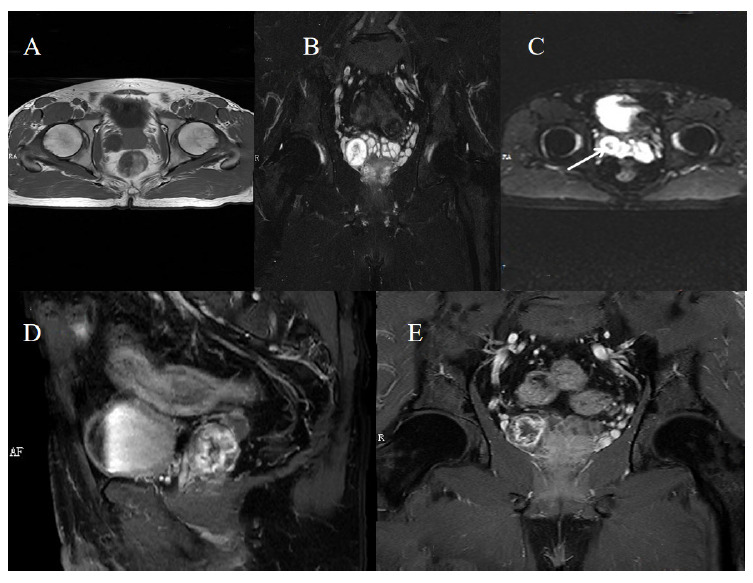

Schwannomas are benign tumors originating from Schwann cells, with seminal vesicle schwannomas being exceedingly rare. This report describes a 54-year-old man with an incidental discovery of a right-sided seminal vesicle mass during a routine ultrasound examination. Further imaging, including MRI and contrast-enhanced CT scans, revealed a well-defined, encapsulated mass with heterogeneous signal intensity suggestive of schwannoma. Histopathological examination confirmed schwannoma, marked by positive S-100 and NSE expression and a Ki67 index of 5%. The patient underwent successful laparoscopic resection without complications and remained asymptomatic for over a month. This case underscores the importance of integrating MRI and histopathological findings to accurately diagnose seminal vesicle schwannomas and guide appropriate surgical management, highlighting the need for increased clinician awareness of this rare tumor.